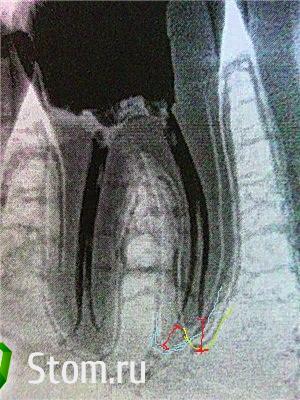

Heineken Опубликовано 18 февраля, 2012 Поделиться Опубликовано 18 февраля, 2012 То что нарисовано что это должно значить, и чем вам не нравится?мне кажется к.каналы в апикальной 1/3 расширены не достаточно и не до верхушки. конечно я могу ошибаться, время покажет Ссылка на комментарий

Kivilgar Опубликовано 18 февраля, 2012 Поделиться Опубликовано 18 февраля, 2012 мне кажется к.каналы в апикальной 1/3 расширены не достаточно и не до верхушки. конечно я могу ошибаться, время покажетТо что недостаточно расширены согласен, а то что не доверхушки спорный вопрос и вопрос методики подготовки каналов. Ссылка на комментарий

Ico Опубликовано 18 февраля, 2012 Поделиться Опубликовано 18 февраля, 2012 (изменено) мне кажется к.каналы в апикальной 1/3 расширены не достаточно и не до верхушки. конечно я могу ошибаться, время покажетСравните протоколы обработки "Cactus" и "Koss" в одном кеисе апекс на 25.04 в этом 30.04 недообработка??Или может проекция невкусная. По картинке можно судить о гиперцементозе где анатомическое сужение и рентгенологическое сильно(1-3.5мм) разнятся. Просят обрабатывать до верхушки,не вопрос даваите колупать цемент))))))))) Изменено 18 февраля, 2012 пользователем Ico Ссылка на комментарий